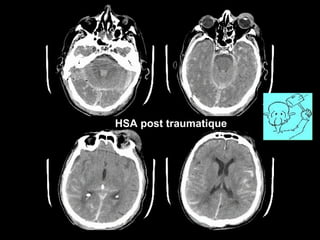

Hémorragie sous-arachnoïdienne (HSA)

= hémorragie méningée (HM)

– post-traumatique

– rupture d’anévrisme, de MAV

– hématome intra-cérébral

souvent associé

Hyperdensité spontanée des espaces sous arachnoïdiens:

citernes de la base et sillons corticaux

HM

HSA post traumatique

Hypersignal des ESA sur la séquence FLAIR